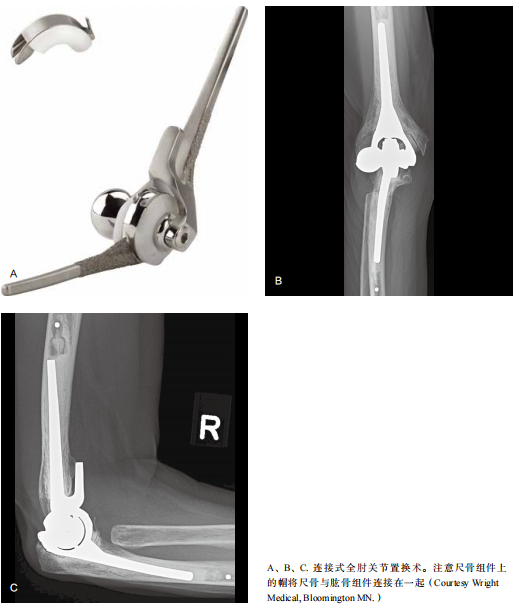

由外科医师决定进入肘关节内部的手术入路。在肱骨远端骨缺损的情况下,采用肱三头肌旁入路,保留肱三头肌附着于尺骨鹰嘴,以保护伸肌装置促进快速的功能恢复。肱三头肌旁入路沿肱三头肌内侧外缘进入关节内。在肘关节僵硬的情况下,为保留肱骨远端充足的骨量,可将肱三头肌从鹰嘴处剥离,充分暴露术野以置入肘关节植入物。肱三头肌可从鹰嘴自内向外方向(Bryan Morrey)或自外向内方向(改良 Kocher)翻起。另外一种入路方式是肱三头肌劈开入路,将肱三头肌在中央劈开,在尺骨近端向内侧和外侧翻起。选择合适大小的植入物。使用专用工具切断肱骨远端、尺骨近端和桡骨近端(如果需要),插入假体试件。急性骨折或轻度关节炎受累时保留桡骨头。试复位检查肘关节屈伸活动,确认植入物的位置正确。如果植入物的位置不理想,非连接式植入物需重新置入。非连接式植入物仅适用于屈肌、伸肌、侧副韧带条件良好充分,无既往畸形,保留或置换桡骨头的年轻患者。当不能满足上述条件或非连接式植入物试件的位置不理想时,应选择连接式植入物。

通常情况下,植入物通过骨水泥固定,并尽可能在肱骨组件的前凸面和肱骨之间植入松质骨。连接式植入物要固定好连接装置,非连接式植入物需修复侧副韧带并与肱骨上髁和假体缝合。如果剥离肱三头肌,则使用非可吸收Krackow 锁定缝线通过钻孔将肱三头肌与鹰嘴缝合。前移尺神经至内上髁前方的皮下组织内,放置引流管,逐层闭合伤口。